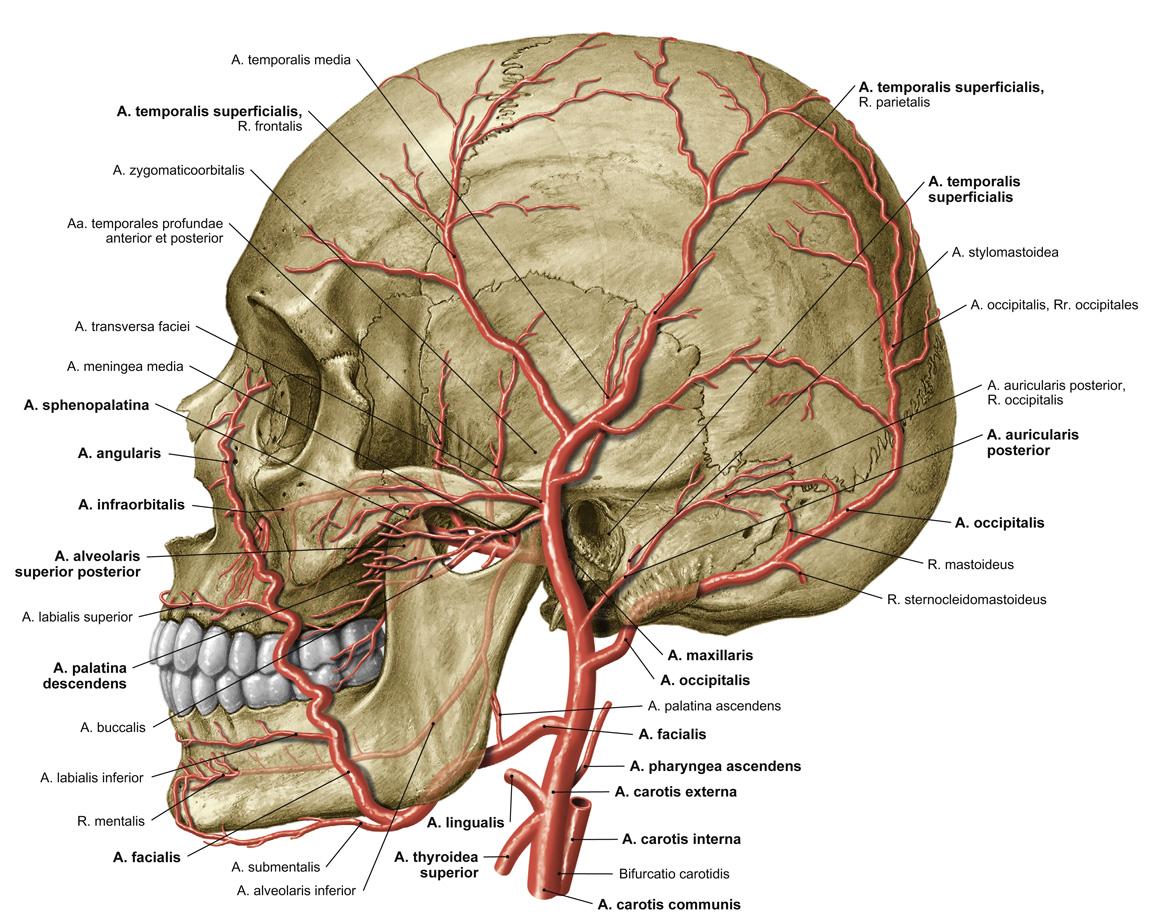

Fig 3.07: a. carotis externa

proc. mastoideus meatus acusticus externus = uitwendige gehoorgang mandibula glandula submandibularis (cyaan) os hyoideum membrana thyroidea (cyaan) os thyroideum?

hypoglussus (XII) -

a carotis communis (ACC)

sinus caroticus a carotis interna (ACI) -

a carotis externa (ACE)

-

ventrale zijtakken

-

a thyroidea superior

a laryngea superior -

n laryngei superioris

beide naar binnenzijde larynx doorboren membrana thyrohyoidea

-

a lingualis

a profunda linguae

-

a facialis

over glandula submandibularis via mondhoek, neusvleugel naar mediale ooghoek anastomose met a. ophtalmica > a. dorsalis nasi

-

dorsale zijtakken

a occipitalis a auricularis posterior

-

mediale zijtakken

a pharyngea ascendens

-

eindtakken

a maxillaris a temporalis superficialis